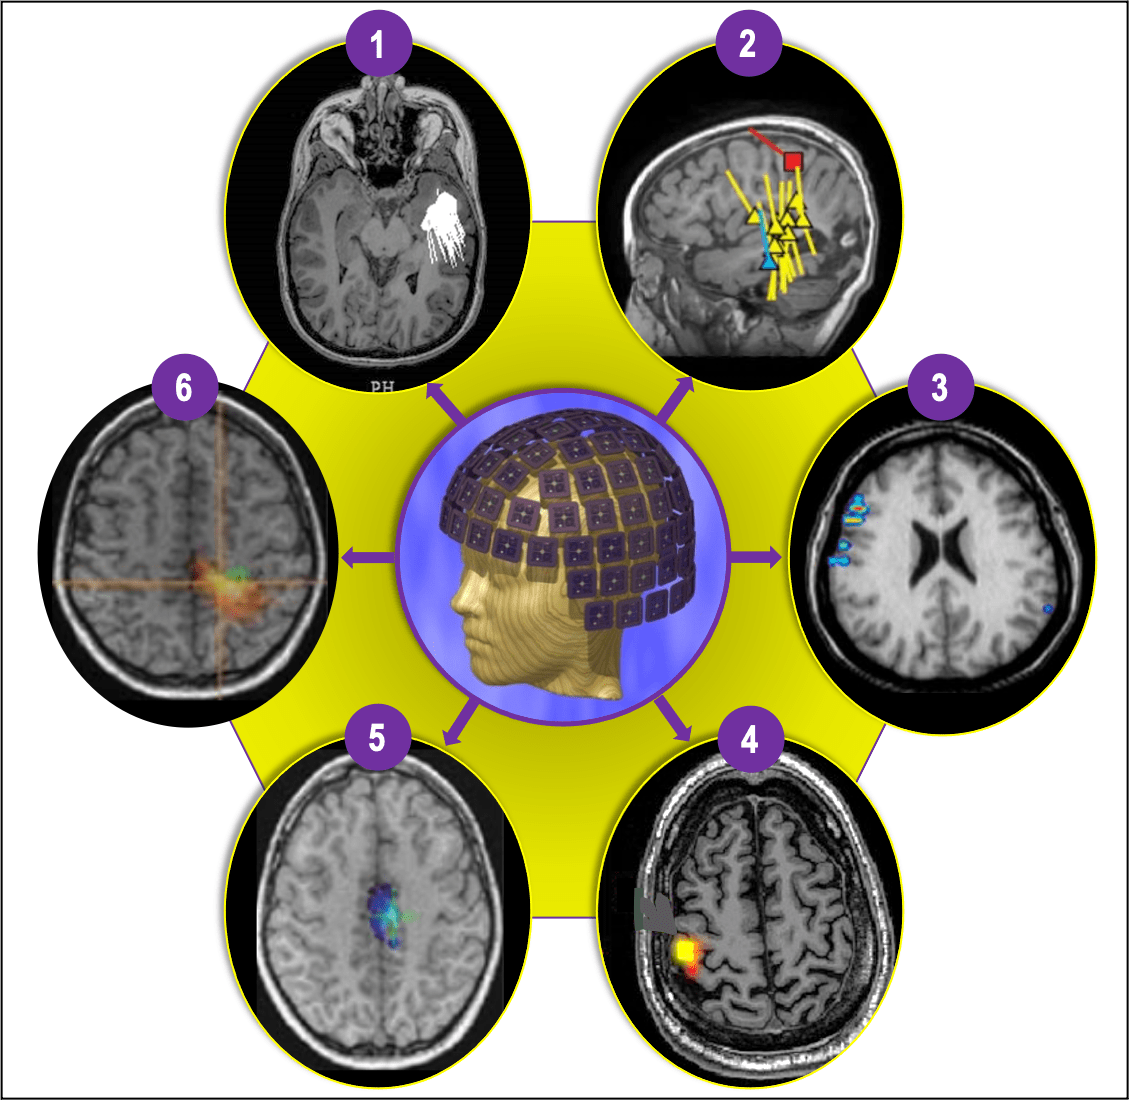

Figure 4 (1-6). The most commonly used and extensively clinically validated form of MEG is magnetic source imaging (MSI) (1 and 2), which is sometimes synonymous with MEG, particularly in epileptology. MSI is a method in which models of the magnetic sources are represented with a dot (or small triangle or square) and tail, where a dot represents a “dipole” (source) location, and a tail represents the source direction. MSI can be used to represent various interictal (yellow), ictal (blue), and functional landmarks (e.g., sensory cortex = red square), creating a neuronavigational map (2) that can be delivered to the planning and neuronavigational software used during the planning and operating phases, respectively. Depending on the type of clinical or research application, MEG data can be processed using a multitude of other techniques that can produce somewhat differently appearing but increasingly similar data displays. Four other more commonly used methods include Current Density Distribution Techniques (3); Minimum Norm Estimate (MNE) (4); Multiple Signal Classification (MUSIC) (5); and Synthetic Aperture Magnetometry (SAM) and excess kurtosis [SAM(g2)] (6).